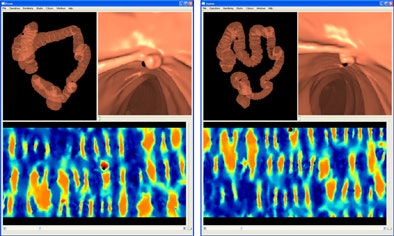

Conformal maps have been used by several groups to "virtually dissect" the colon and produce flattened 2D images of the endoluminal surface -- techniques that were developed to speed interpretation, the authors explained. Typically applied to surface mesh triangulations to simplify the representation of a 3D object, they are used to map 3D surfaces to a 2D space while preserving local angles. Those surfaces, or S, can be parameterized using a discrete conformal mapping method, which maps the entire surface while preserving the appearance of local structures such as polyps and haustral folds.

![]() |

| The image above depicts the principle of registration between endoluminal surfaces S of the colon derived from prone and supine CT colonography using cylindrical 2D parameterizations P. The color scale indicates curvature-based measurements on the 3D surfaces, here shape index. These measurements can be used to compute the transformation between the two cylinders using nonrigid registration. All images courtesy of Holger Roth, PhD. |

To extract the endoluminal colonic surface S, the inflated lumen L is segmented using the method described by Slabaugh et al, the group wrote. The endoluminal colonic surfaces are then modeled as triangulated meshes on the gas-tissue border in the CTC images.

Curvature information from the original 3D surfaces is used to determine correspondence. A nonrigid registration method is used to align the local structures accurately.